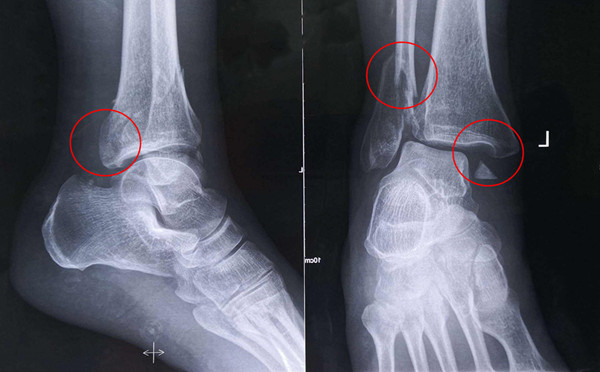

踝關節骨折在X影像上的表現有很多種。如內踝骨折和外踝骨折,我們可以在影像上看到骨折處的骨折線是不連續的。還有后踝的骨折,內踝、外踝、后踝聯合在一起發生的骨折,我們稱之為“三踝骨折”,這些都是在X影像上能夠顯示出來的。

【醫療科普】Pilon骨折

有一種特殊類型的踝關節骨折,可能在X影像平片上就不能顯示出來,它就是脛骨的關節面往里塌陷,我們又稱之為叫“Pilon骨折”。當它往里塌陷后,我們在X影像平片上可能看不出來它是否塌陷,但是我們在CT上可以360°看到踝關節的影像,這樣就可以看出患者是否存在踝關節塌陷的骨折。同樣道理,我們在做Pilon骨折手術的時候,普通二維的X影像并不能判斷我們手術復位情況的好壞,這個時候如果醫生手上有能夠照三維影像的工具,那么對于醫生的準確手術是非常有好處的。